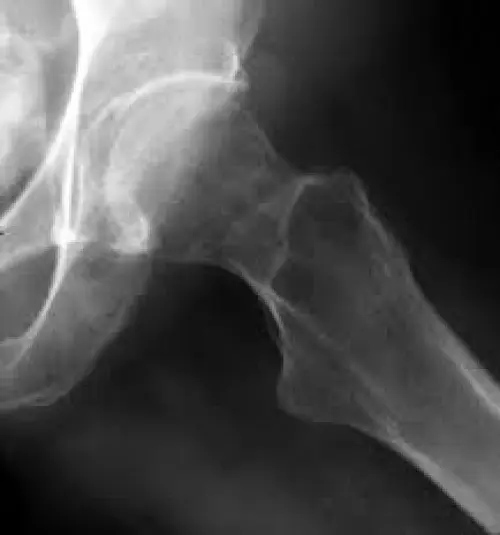

OssaL’osteoporosi può essere prevenuta con 20 minuti al giorno di esposizione ai raggi solari. Il suggerimento altamente qualificato proviene dalla Società Italiana dell’Osteoporosi, del Metabolismo Minerale e delle Malattie dello Scheletro (Siomms). L’esposizione al sole purché sia moderata, stimola la produzione di vitamina D. Non è un elemento di poco conto, basti solo considerare che in Italia i 70% della popolazione sofffre di ipovitaminosi D, carenza di calcio e conseguente fragilità ossea. A soffrirne maggiormente sono le donne.

In realtà i fattori che aumentano il rischio di osteoporosi possono essere contrastati efficacemente sia con l’esposizione settimanale al sole per 20 minuti al giorno, con braccia, viso e gambe scoperte e sia con la dieta che privilegi alimenti quali salmone affumicato, sgombro sotto sale., olio di fegato di merluzzo e anguilla. Insomma l’esposizione al sole per la vitamina D e la dieta lavorano sinergicamente per prevenire questo problema.